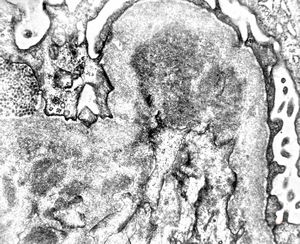

M,22y. | type II membranoproliferative glomerulonephritis